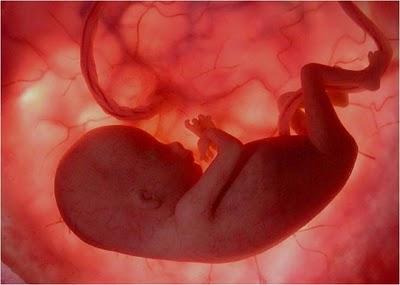

A LA 16ª SEMANA DE GESTACIÓN YA CASI TODOSSUS ÓRGANOS ESTÁN DESARROLLADOS.

LOS OJOS AÚN ESTÁN CERRADOS, SUS MANOS Y PIE COMIENZAN A MOVERSE, AUNQUE SU MADRE CASI NO LO PERCIBE AÚN.